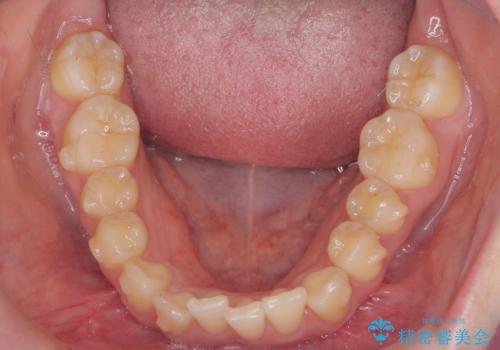

- 前歯のねじれを主訴に来院。

前から2番目の歯がねじれて下の歯の内側に入っていました。

また、奥歯のかみ合わせが上の奥歯が若干前に並んでおり、それで前歯が入りきらずにねじれていました。

歯を抜かずに奥歯を後ろに下げてマウスピースで矯正しています。

上の奥歯を後ろに下げて前歯のねじれを治すスペースを確保しました。

奥歯を後ろに下げるために、矯正用インプラントを使用しています。